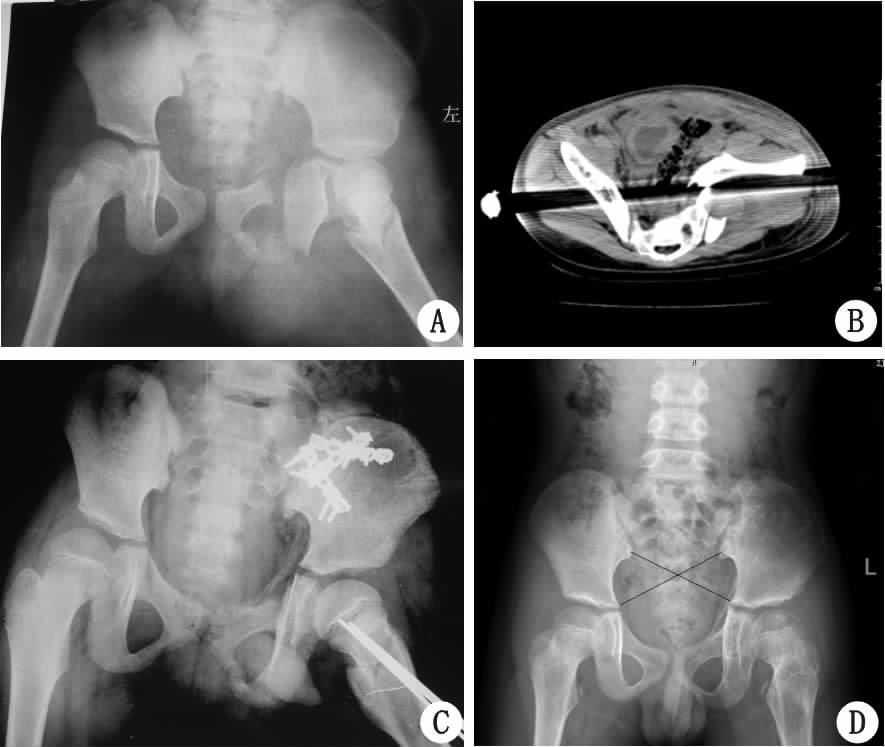

1.2 治疗方法入院后首先实施创伤控制,通过补液、输血等纠正休克状态。急诊予胸腹带加压包扎患儿骨盆,由相应专科积极处理内脏损伤,于伤后3~19 d(平均6.5 d)实施骨盆手术。手术方法:患儿均采用全身麻醉。9例切开复位内固定者采用仰卧位,骨盆后环有骨折的一侧臀部垫高,采用髂腹股沟入路,切开髂前上棘软骨后,沿着髂骨内外缘向深处剥离,直至显露骶髂关节前后缘。术者在骶髂关节后缘予骨膜剥离器翘拨骨折处,助手予2把布巾钳夹住髂前上棘,向前向内提拉以协助复位。复位后予重建钢板(图 1)或松质骨螺钉固定(图 2)。后环骨折复位固定后,术者双手扶持双侧髂前上棘向内挤压,可进一步复位骨盆前环骨折。本组另1例患儿骨盆骨折合并会阴部皮肤撕脱伤,在当地医院牵引治疗,于伤后15 d转来本院,会阴部皮肤大片缺如,创面绿脓杆菌感染,局部软组织条件无法实施切复内固定,故于伤后19天在麻醉下行闭合复位Illizarov支架外固定(图 3)。

| A、B:术前X线片及三维CT示,左耻骨上下支骨折,左髂骨翼骨折,左股骨颈骨折,c:术后X线片示,髂骨翼骨折切开复位后重建钢板固定,左股骨颈骨折闭合复位克氏针固定;D:随访3年后X线片示,骨盆形态良好,骨盆对角线差异仅为0.3 cm 图 1 男,5岁6月龄 |